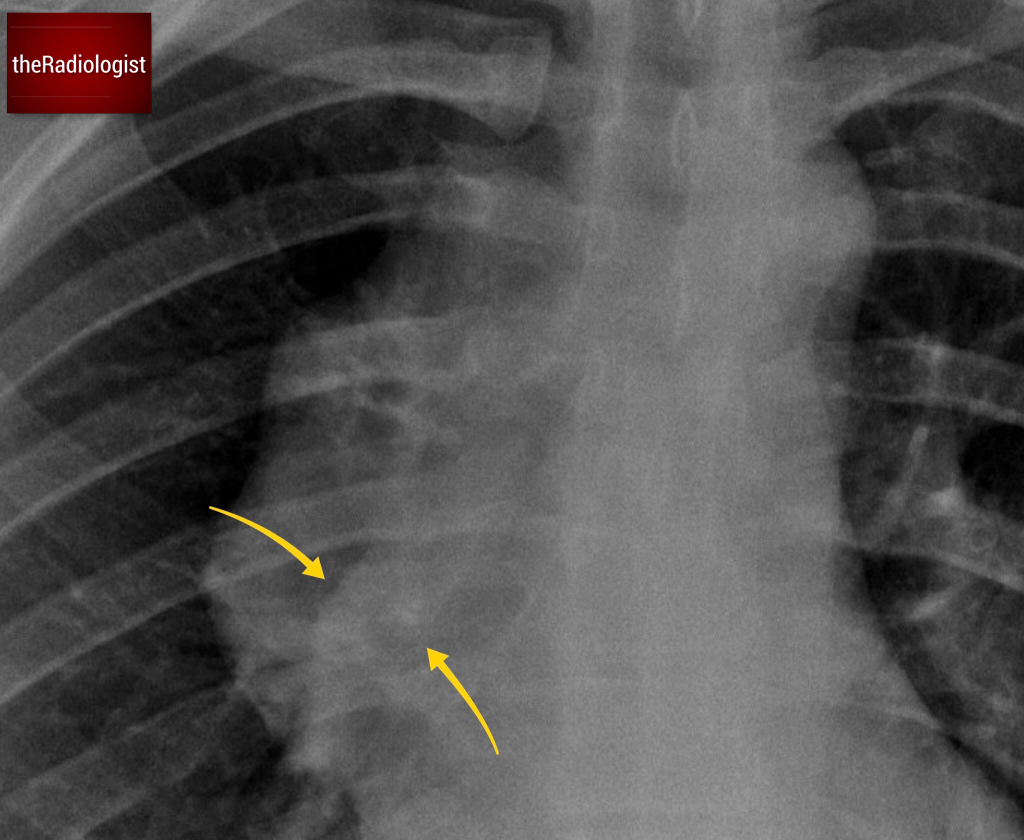

Take a closer look at the X-ray. Through the abnormal mass, you can still make out the right hilar vessels. This tells us something crucial:

• If the mass were in the middle mediastinum, we wouldn’t be able to see the hilum because it would obscure those structures.

• This phenomenon is called the hilum overlay sign.

Most central lung cancers are located in the middle mediastinum or involve the hilar region, and although there handful of occasions where I have seen lung cancers present with a hilum overlay sign on X-Ray, it makes lung cancer much less likely. Instead, we need to consider a mass in either the anterior or posterior mediastinum.

Statistically, anterior mediastinal masses are the most common culprits in cases with a hilum overlay sign although there are times where it can be caused by a posterior mediastinal lesion. Make sure you look for signs of a posterior mediastinal lesion such as loss of the contour of the descending aorta or an abnormality of a paraspinal line: in this case these features of a posterior mediastinal lesion are absent.

Look through the mass and you will see the right hilar vessels: if you can see the vessels through a hilar mass (yellow arrow) this is called the hilum overlay sign and points you away from a middle mediastinal lesion.